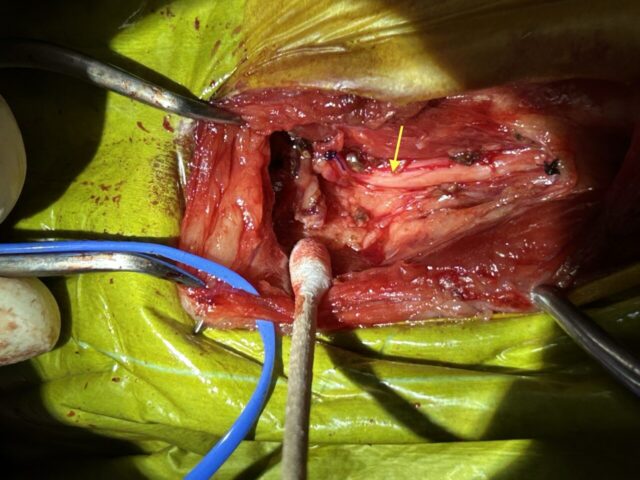

この際、血管には神経(黄色矢印)が併走しているため、神経は損傷しないように注意が必要です。

切除後の写真です。神経(黄色矢印)が温存されているのが分かります。

術後大きな問題はなく、3日で退院しました。

病理診断は頸動脈小体であり、完全に切除できていました。